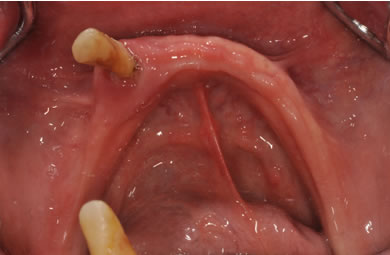

骨再生スピードインプラント治療+AGC連結セラミック治療

| 性別/年齢 | 女性 / 57歳 | ||||||||||||||||||||||||||||||||

| 主訴 | 全体的に歯が無いので相談したい。 | ||||||||||||||||||||||||||||||||

| 治療方針 | 骨再生療法にて骨量を回復するとともに軟組織も移植し、機能的回復だけでなく審美的回復も行う。 | ||||||||||||||||||||||||||||||||

| 治療内容 | インプラント12本(サイナスリフト+GBR+抜歯即日スピードインプラント+遊離歯肉移植)、AGCハイブリッドセラミック連結ブリッジ2装置(上顎・下顎)、テンポラリーインプラント2本 | ||||||||||||||||||||||||||||||||

| 総治療費 | 6,019,650円 | ||||||||||||||||||||||||||||||||

| 治療期間 | 1年0ヶ月 |